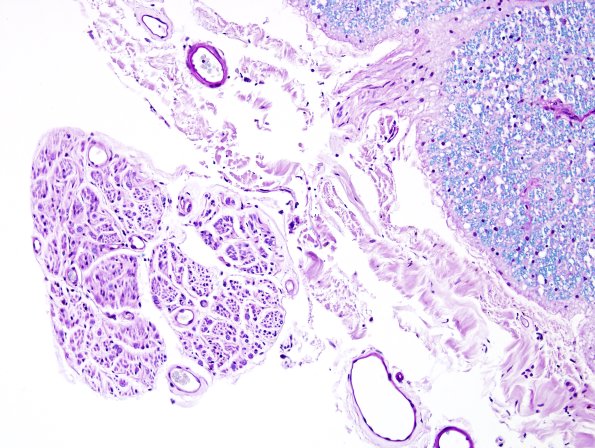

1C4 ALS (Case 1) N12 LFB-PAS VR 20X 1

Notice the size, pallor and axon loss in the ventral root. (LFB-PAS)